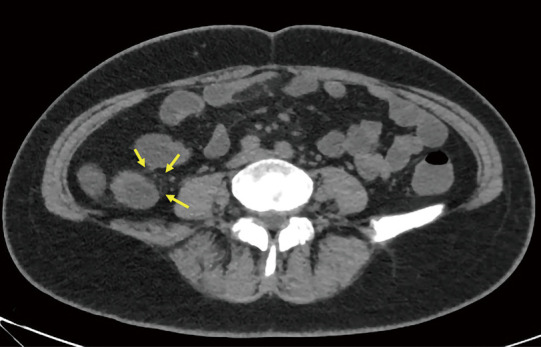

Background: Creeping fat (CF), a characteristic structure of Crohn's disease (CD), is closely associated with surgery and prognosis but lacks a unified imaging assessment standard, and endoscopic and serological indicators have limitations in evaluating extra-intestinal lesions. The study aimed to explore the correlation between computed tomography (CT) value distribution changes of mesenteric-surrounding fat in CD and disease activity.

Methods: In this study, we retrospectively analyzed CT enterography (CTE) images from 47 pathologically confirmed CD patients and 25 randomly selected controls with suspected inflammatory bowel disease (IBD). Quantitative measurements were obtained for mesenteric adipose tissue density (mean of CT values) along key anatomical landmarks including the mesenteric root, superior mesenteric artery, inferior mesenteric artery, perilesional regions, intestinal stricture, and adjacent branching vascular spaces. Other evaluated parameters included bowel wall thickness, CT attenuation, enhancement patterns, and CF grading. Qualitative evaluations were made by comparing with endoscopic, serological, and histopathological results and simplified CD activity index (CDAI) scores. A patient with concurrent anal fistula underwent magnetic resonance imaging (MRI) examination to compare its detection efficiency of fistula with that of CT examination.

Results: Significant inter-group differences were found in non-contrast mesenteric fat attenuation, mean ΔCT (difference in Hounsfield units between contrast-enhanced CT and non-contrast CT scans) enhancement, bowel wall thickening, mucosal enhancement, CF grading, intestinal stricture, and serological parameters (P<0.05). The moderate-to-severe activity group had the highest mesenteric fat density in the venous phase [mean ΔCT >20 Hounsfield units (HU), P<0.05], especially around lesions. There was a positive correlation between mesenteric fat CT values and images of diseased bowel segments. The mean value of the venous phase ΔCT of the lesion and the mean of the intestinal wall venous phase ΔCT value and intestinal wall stratification were positively correlated (>0.6, P<0.05). ROC analysis showed that the venous-phase ΔCT of perilesional adipose tissue had excellent diagnostic performance [area under the curve (AUC) =0.964] for moderate-to-severe activity CD, with 95.8% sensitivity and 87.5% specificity. The diagnostic efficacy of the venous phase in the vascular space around the lesion ranked second (AUC =0.943). MRI showed superior detection of the anal fistula to that of CT in one patient. Multivariate analysis confirmed it as an independent predictor for moderate-to-severe active CD (P<0.05).

Conclusions: Changes in mesenteric adipose tissue CT values and CF classification can distinguish CD from other IBD, suggesting their utility as another noninvasive diagnostic method for predicting the inflammatory activity of CD and evaluating the scope of surgery.